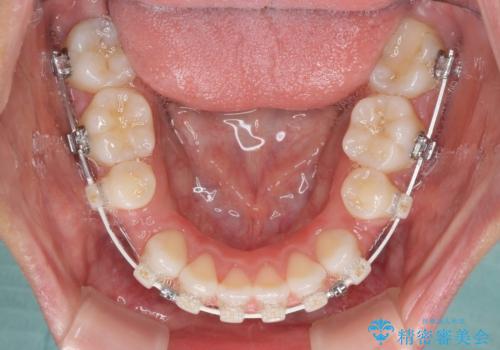

- 矯正装置

- ハーフリンガル

- 2年9ヶ月

- 治療回数

- 10-30回

表側のワイヤー矯正に比べると治療期間は長く、費用も高額となりますが、どうしても目立たせたくないという方にはお勧めの抜歯矯正です。